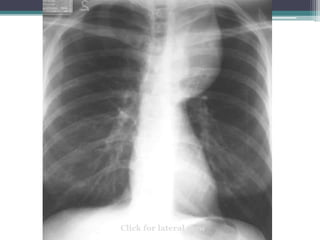

Which compartment do you think this mass is in?

Click for answer

Cervicothoracic sign

โ€ข Answer: Mass lies in anterior mediastinum. We

know this because it disappears at the level of the

clavicle where it extends into the neck.

โ€ข This particular example is Non-Hodgkins lymphoma